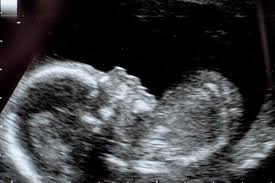

4. 임신 시 태아 초음파 검사

- 태아 상태 확인을 위한 복부 초음파는 임신 중기(20주 전후) 이후 정기적으로 진행